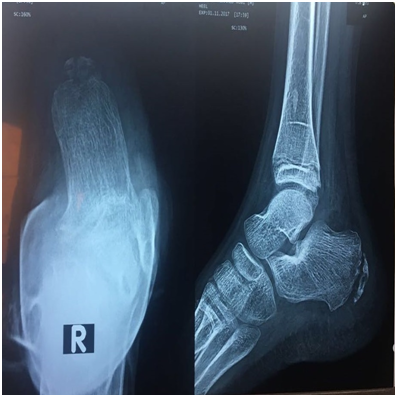

A well-built 14 years old boy presented with severe constant right heel pain which was increased by physical activity, and relieved partially by NSAIDs. He was physically active. The patient denied trauma or fever. He reported no history of other musculoskeletal symptoms. At that time physical examination was apparently normal apart from mild swelling and localized tenderness over the posterior right heel. Laboratory tests were significant for elevated ESR (69 mm) and CRP (12.5 mg/dl). CBC, liver & kidney function tests were normal. RF was negative. X-ray heel findings showed fragmentation &increased density of calcaneal apophysis. Although the patient’s clinical history, the overuse of sports activity, together with the radiographical findings were in line with calcaneal apophysitis (sever’s disease), the unexplained elevation of ESR & CRP made us to proceed to magnetic resonance imaging (MRI)to exclude osteomyelitis. The MRI demonstrated oedema of the calcaneal apophysis with patchy oedema of the calcaneal bone as well as the overlying soft tissue that consistent with Sever disease (Figure 1). Oral anti inflammatory medication was prescribed in addition the patient was advised to use heel raise shoe orthoses and to restrict sports for 6weeks.

Figure 1 legend   MRI demonstrated oedema of the calcaneal apophysis with patchy oedema of the calcaneal bone as well as the overlying soft tissue.

Figure 5 legend   x-ray of Rt heel show evidence of osteomyelitis.